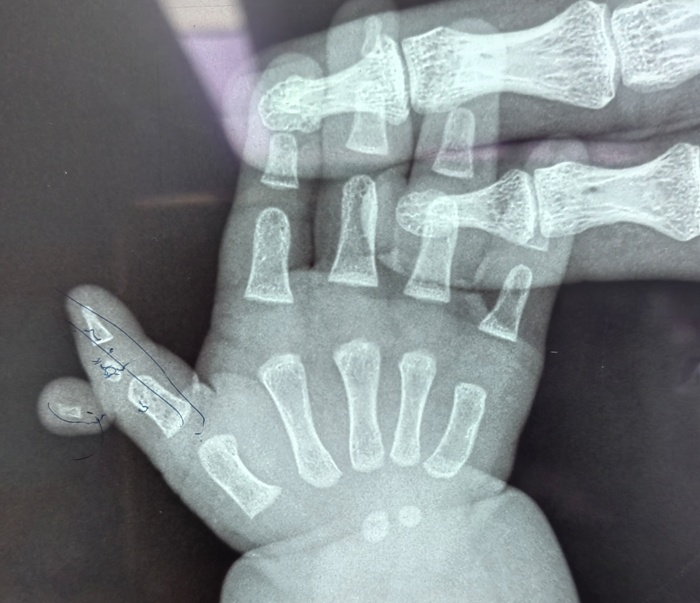

近日,在德州扑克游戏网 的手术室内,一场特殊的手术正在进行。手术台上,一位仅六个月大的女婴安静地躺着,她的右拇指旁多出一个发育不全的指节,这个多余的手指像影子一样跟随着拇指移动,同时右拇指又长又歪,虽然不影响生命,但却严重影响了患儿手部功能的正常发育。

据孩子的妈妈介绍,孩子一出生,他们便发现了异常,孩子右手拇指较正常手指明显歪斜并且比左手的拇指要长,且在这根手指外侧,还多出来一截手指。多余的手指长在拇指指间关节处,虽然有指甲、有手指形态,但因为发育不全而缺乏自主活动能力。考虑到孩子年龄太小,家长一直未敢轻易做出治疗决定。

手术当天,骨科医护人员制定了周密的手术方案。在精准地切除了多余的手指后,切除了Delta骨块,修复韧带并予克氏针固定,对畸形的拇指进行了矫正。最终,患儿的右拇指恢复了正常形态。术后,患儿在医护人员的精心护理下逐渐康复,小手也变得更加灵活。医护人员高超的技术和优质服务,也赢得了家长由衷的感谢。

据骨科主任高凤奇介绍,三节拇指合并多指畸形并不常见,正常的多指多在一周岁以后手术治疗,多指的切除相对简单,但是三节拇的矫形较为复杂。合并Delta骨块的三节拇指合并多指一定要早期治疗,最早可以在六个月即可手术,越早做手术效果越好,德州扑克游戏网 儿童骨科是长春市“十四五”医学重点专科,是吉林省内唯一一家专业的儿童骨科科室,历史悠久、综合实力雄厚。对于常见的儿童先天性肌性斜颈、多指、先天性髋关节脱位,以及复杂的四肢畸形、骨关节感染等有着丰富的治疗经验。